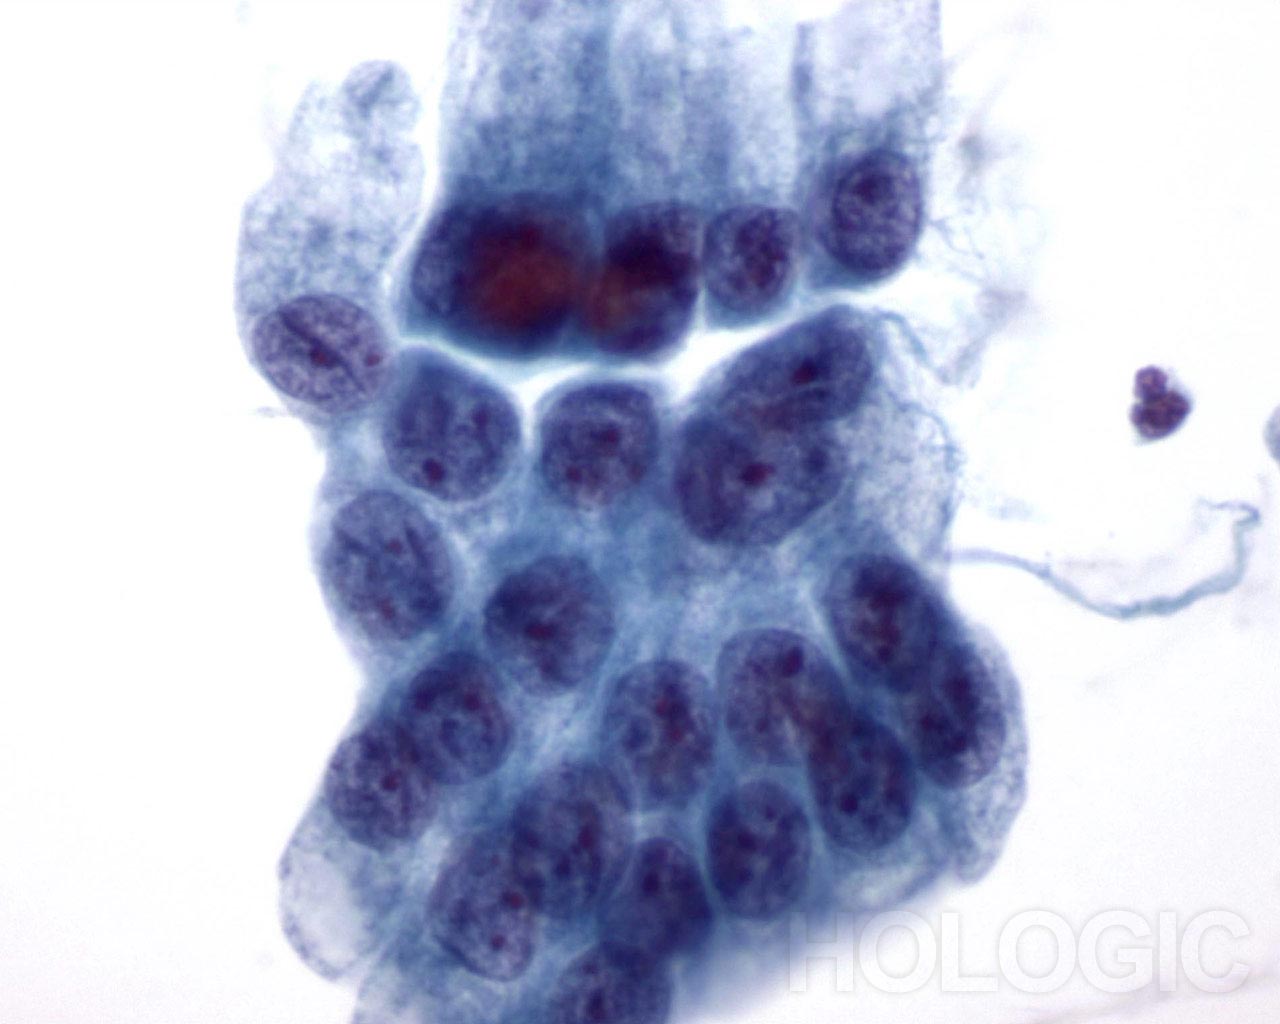

Abbildung 21

Bürstenabstrich des Gallengangs, reguläres Gallengangsepithel.

Bienenwabenstruktur des Epithelzell verbandes ohne Atypie.

40x